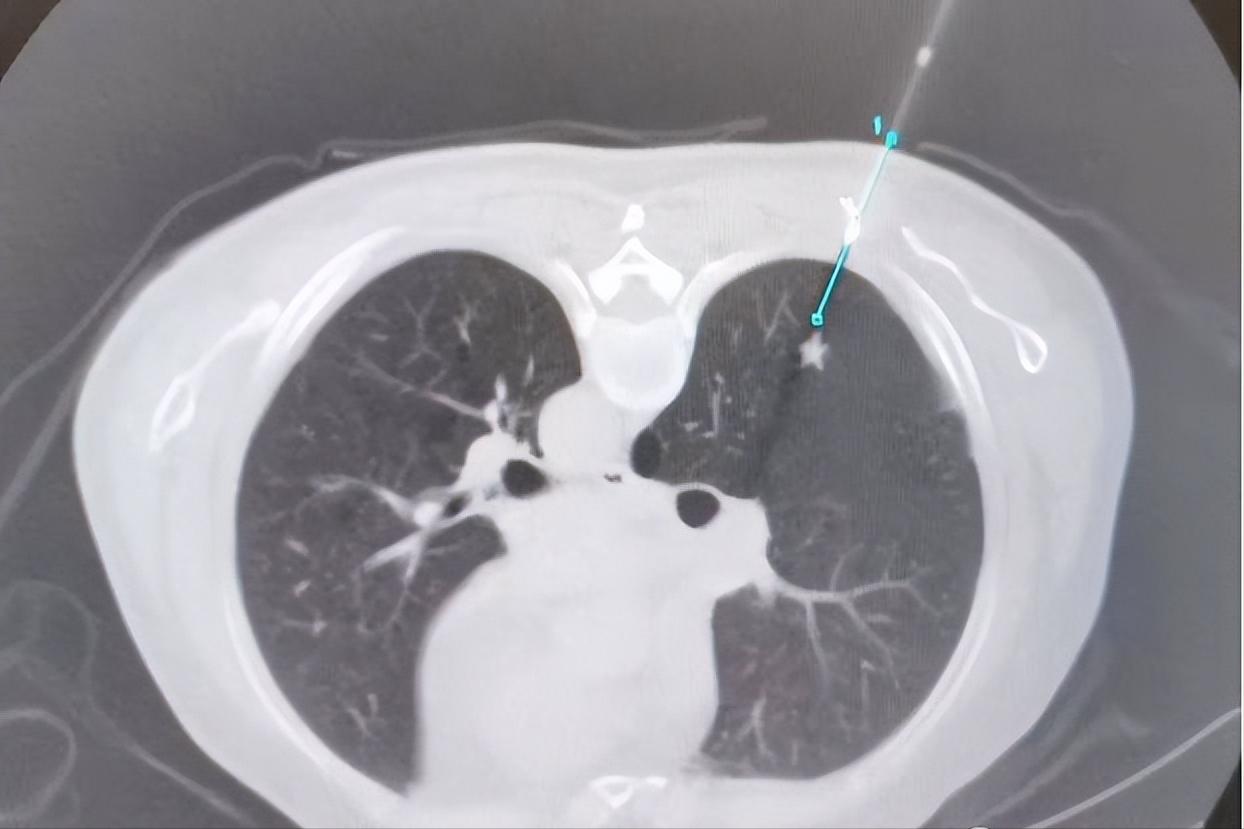

入院后完善检查,胸部CT显示右肺下叶背段实性结节,边缘毛刺,形态不规则,高度考虑恶性病变可能。

设计穿刺路径: